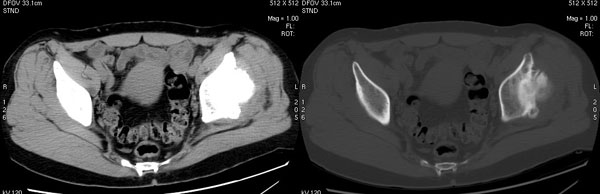

以下是引用jiajie在2006-7-14 17:19:00的发言:[br]ct所见:双侧髋关节不对称,左侧关节间隙变窄,关节面毛糙。左侧股骨头变形、无明显变小,前上缘与髋臼融合,融合处骨质明显增生硬化,并见数个小囊变影。股骨头下端与股骨颈交界部见囊样变,邻近肌肉内见囊样密度减低区,ct值24hu。右侧髋关节形态未见异常。[br][br]ct诊断:左侧髋关节结核可能,请结合临床资料进一步分析。

以下是引用lihuuuu在2006-12-5 10:14:00的发言:[br]定位像示:左侧髋臼变浅,倾斜度加大,髋臼外上缘呈波浪状不规则,骨质增生硬化,髋关节上缘间隙明显变窄,股骨头向外上轻度移位。轴位像示:左侧股骨头变形,前上缘与髋臼融合,融合处骨质明显增生硬化,并见数个小囊变影。股骨头下端与股骨颈交界部见囊样变,邻近肌肉内见密度减低区,ct值24hu,内缘见弧形高密度钙化影。右侧髋关节形态未见异常。[br]ct诊断:左侧髋臼发育不良[br] 左侧股骨头缺血性坏死[br] 左侧肌肉内低密度影伴有高密度钙化-考虑早期骨化性肌炎[br] [br]“我认为在描述上已经写了肌肉部分,印象诊断里应该写主见”[br]